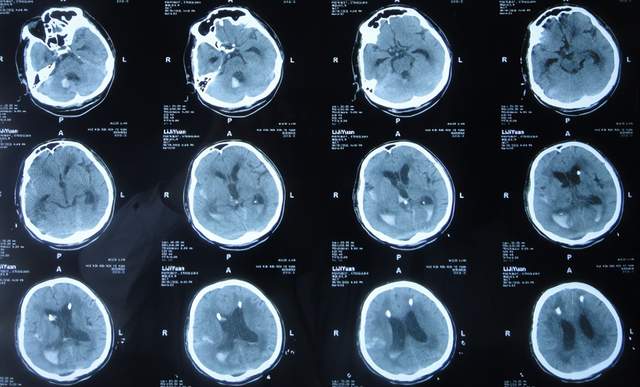

出院1个半月后,因患者病情无改善,家属想做脑室腹腔分流术,于2021年12月22日前往上级的山东省滨州市某三甲医院就诊,查头颅CT示脑积水(图-10);但腰椎穿刺检查示颅内压低;胸部CT有肺部脓肿(片子丢失),暂时给予抗感染治疗。

图-10:2021年12月22日头颅CT

给予抗感染治疗个月后即2022年1月17日,肺部脓肿明显变小(片子丢失),查头颅CT仍脑积水(图-11),未给予脑室腹腔分流术,建议暂时回家休养,但患者意识仍不好,不能走路,不能说话,体型变消瘦。

图-11:2022年1月17日头颅CT

2022年2月16日(脑出血后5个月零14天,继发脑积水4月余),为治疗脑积水,家属通过网上查询,并经确认后来到北京北亚骨科医院的李小勇脑脊液科。

入院时查头颅CT示脑积水(图-13);肺部CT示肺部感染(图-14)。

图-13:2022年2月16日头颅CT

入院次日,给予脑室外引流术,查头颅CT示脑室外引流术后状态(图-15)。

图-15:2022年2月17日头颅CT